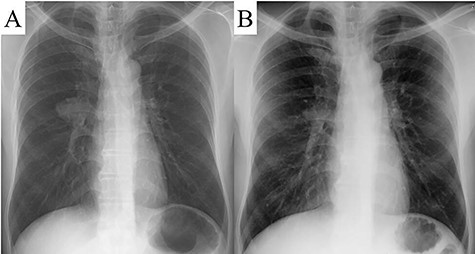

The patient was a 48-year-old man, in whom a round mass lesion was detected in the hilum of the right lung by chest radiography performed at an annual health checkup (Fig. 1A). The image of this mass lesion had been interpreted as a normal view on chest radiography performed at his annual health checkup one and a half years previously (Fig. 1B). The mass detected by radiography was also detected by computed tomography (CT), as a 3.5 cm low-attenuated mass with a circumscribed margin in a fissure of the right lung (Fig. 2A, B). On magnetic resonance imaging (MRI), this mass lesion was displayed as a high, low and low signal mass on the in-phase of T1-weighted imaging (WI), out-of-phase of T1WI and T2WI, respectively (Fig. 2C–E). The mass lesion was not clearly enhanced by fat-saturated contrast-enhanced T1WI with extracellular gadolinium contrast material (gadoterate meglumine; Magnescope®; Guerbet, Villepinte, France) (Fig. 2F). The radiological observations were highly suggestive of a hamartoma.

A round mass was detected in the hilum of the right lung by chest radiography (A). A chest radiograph taken one and a half years previously displayed a normal view (B).